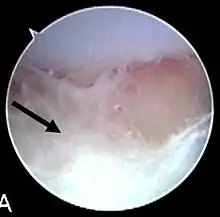

| Septic arthritis as seen during arthroscopy[1] The arrow points to debris in the joint space. | |